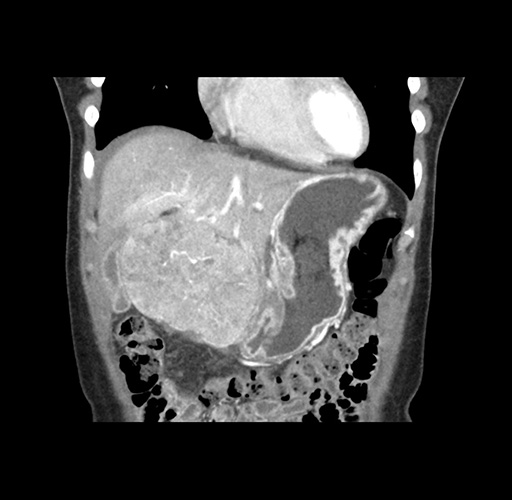

Imaging Analysis

Look through the patient's CT scan to identify any areas of concern for the necessary procedure.

Based on your CT findings, which issue(s) would give reason for "planned slowing down moment(s)" in this case?

Considering a standard left lateral sectionectomy procedure, what step(s) of the operation would you do differently in this case ?